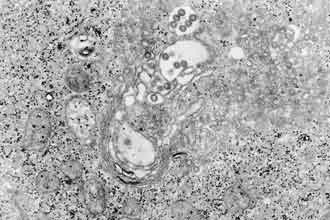

RVFV病毒表面含有Gn和Gc两种囊膜蛋白,是负责病毒与细胞粘附和膜融合的关键蛋白。高福团队曾率先解析白蛉病毒属重症伴血小板减少综合征病毒(SFTSV)与RVFV的Gn的结构。针对RVFV的感染,研究团队首先检测到一例RVFV感染患者体内存在高水平的Gn和Gc的结合抗体,说明Gn与Gc可以同时激发人体的免疫反应。因此以Gn和Gc为“诱饵”,研究团队从康复患者的体内筛选到8株结合Gn及1株结合Gc的抗体。然后,通过细胞水平的中和实验,研究团队发现靶向Gn的抗体具有极高的中和活性。相比之下,分离到的Gc抗体则显示出较弱的中和活性。相应地,在小鼠感染模型上,Gn特异性抗体也显示良好的预防和治疗RVFV感染的效果,而Gc抗体则无明显保护作用。研究团队进一步通过流式分析发现Gn抗体可以阻断Gn蛋白以及RVFV病毒粒子对易感细胞的粘附,而Gc抗体则没有这样的效果。这些结果说明Gn抗体通过结合到病毒粒子上的Gn,阻断病毒与细胞的粘附,从而中和RVFV的感染。研究团队分别解析了Gn与4株中和抗体的复合物结构,鉴别出Gn的结构域I(domain I, DI)上存在3个中和抗体结合位点(A,B与C),其中抗原位点A与B是中和抗体的结合热点,超过半数的Gn抗体都靶向A与B。